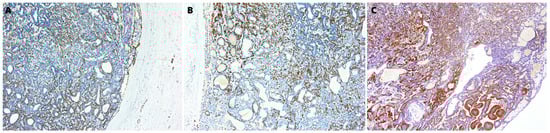

2.2. Pathology